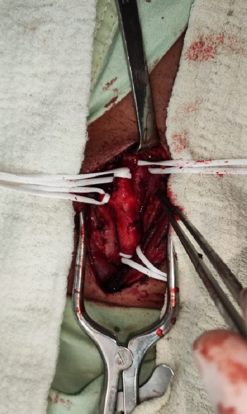

Consulta especializada, doppler vascular, escleroterapia quimica, escleroterapia por radiofrecuencia.